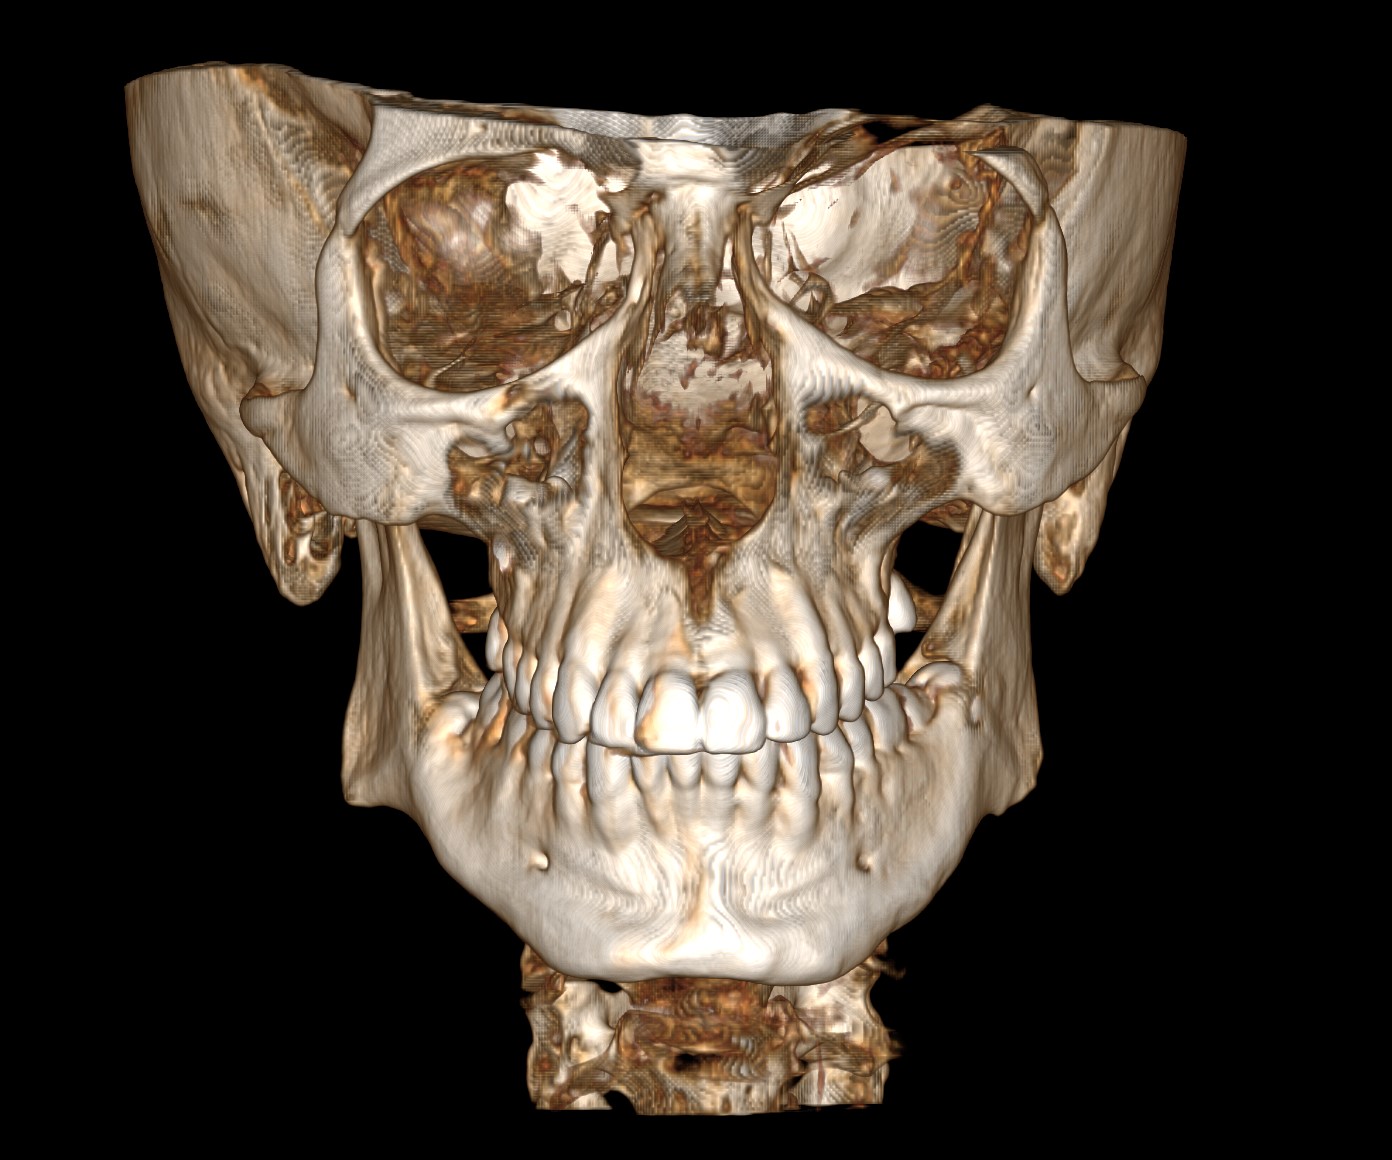

CBCT (Front + Side) + OPG (Old Before & New After braces) (need decompensation)

My Analysis (Based on CBCT):

- Gonial Angle: 131.8°

- Inter-molar Width: ~34.7mm (Narrow palate, teeth in compensation).

- Face Type: High divergence, nasolabial folds, poor midface & infraorbital support)

- Bimax (BSSO + Lefort 1) with CCW Rotation: I need to close that 132° angle and get projection.

- Skeletal Expansion (MARPE/MSE/FME/SARPE): My inter-molar width is ~34.7mm. I’m debating and honestly I don't have much knowledge about this. I want to maximize midface widening and cheekbone support. Given I'm planning Bimax anyway, which one would you guys suggest?

- Midface support: I’m leaning towards custom PEEK inframalar/infraorbital implants but I want to know if I can avoid paranasal implants by performing a High LeFort I cut and advancing the ANS, or maybe eventually both?

- Jaw/Angles: I definitely lack bone mass here too. I'm considering custom jaw implants (wraparound or angles), but I’m worried about two things: 1) Is it even possible to do Bimax + Midface + Jaw implants in a single op? 2) The budget might explode.

- Genioplasty: Undecided. If the CCW rotation provides enough projection, I might skip it, but idk tbh.